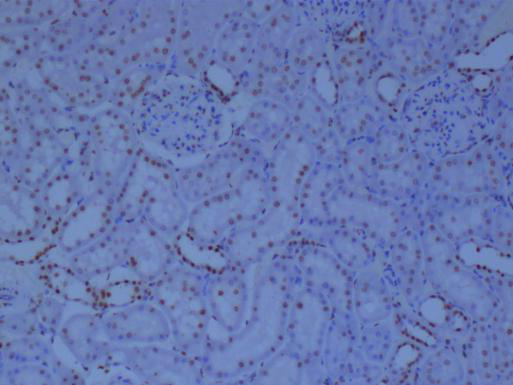

冰凍切片實驗是生物學、醫學等領域中常用的一種實驗技術,主要用于觀察和研究生物組織的微觀結構。在進行冰凍切片實驗時,掌握一些關鍵的技巧對于獲得高質量的切片至關重要。本文將詳細分享一些冰凍切片實驗的技巧,幫助讀者更好地進行實驗。